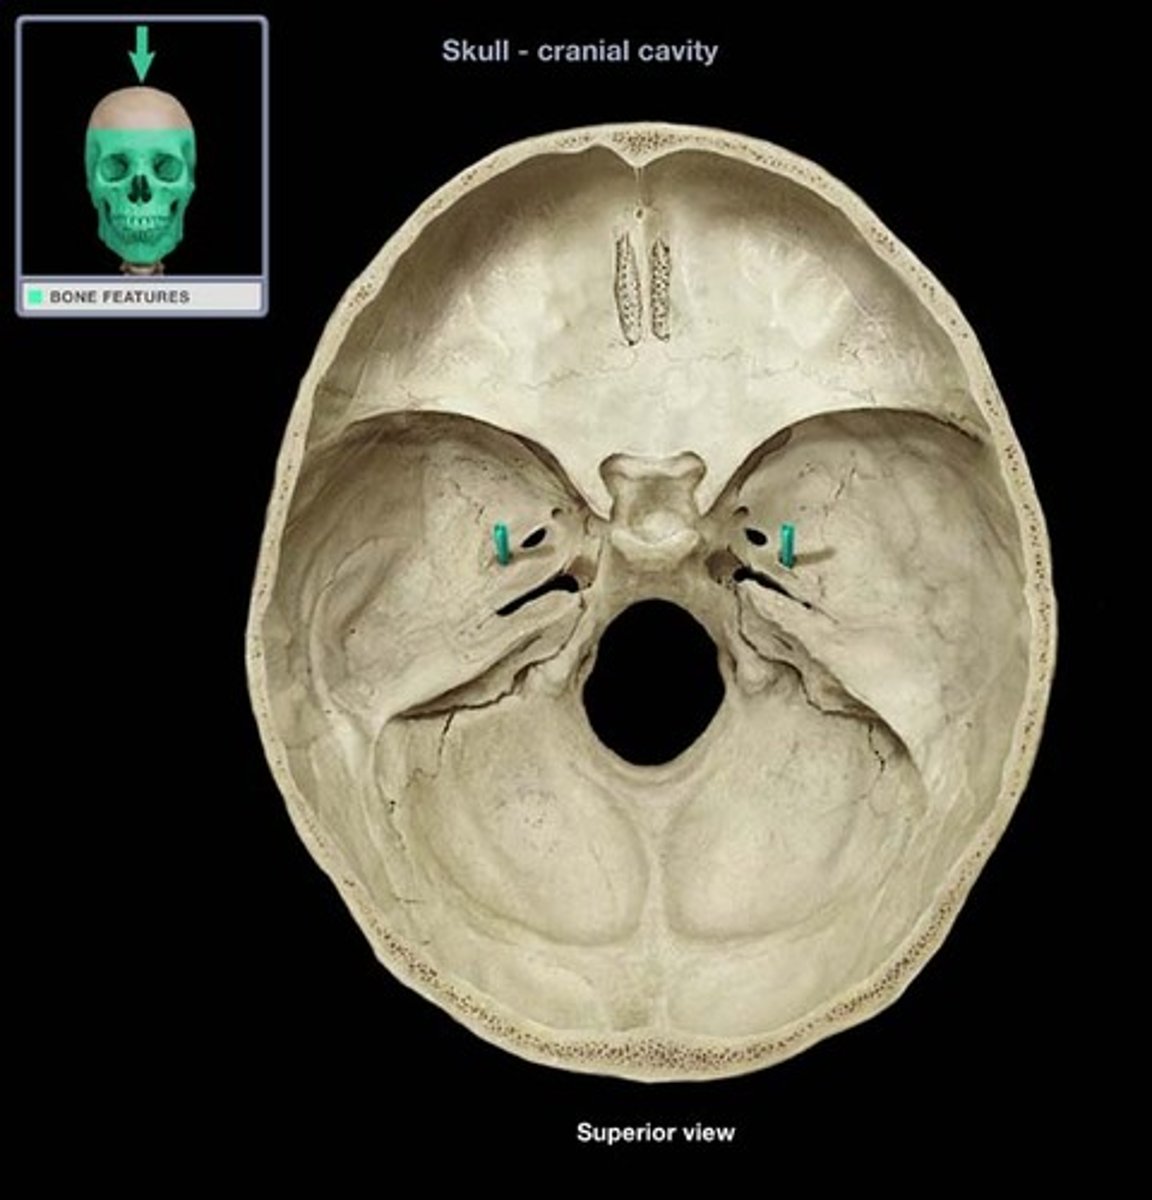

anterior cranial fossa

posterior cranial fossa

middle cranial fossa

cribriform plate

superior orbital fissure

optic canal

foramen rotundum

foramen ovale

foramen spinosum

foramen magnum

jugular foramen

hypoglossal canal inferior view

hypoglossal canal superior view

groove for transverse sinus

groove for superior sagittal sinus

internal occipital crest

sella turcica

mandibular fossa

foramen lacerum

carotid canal